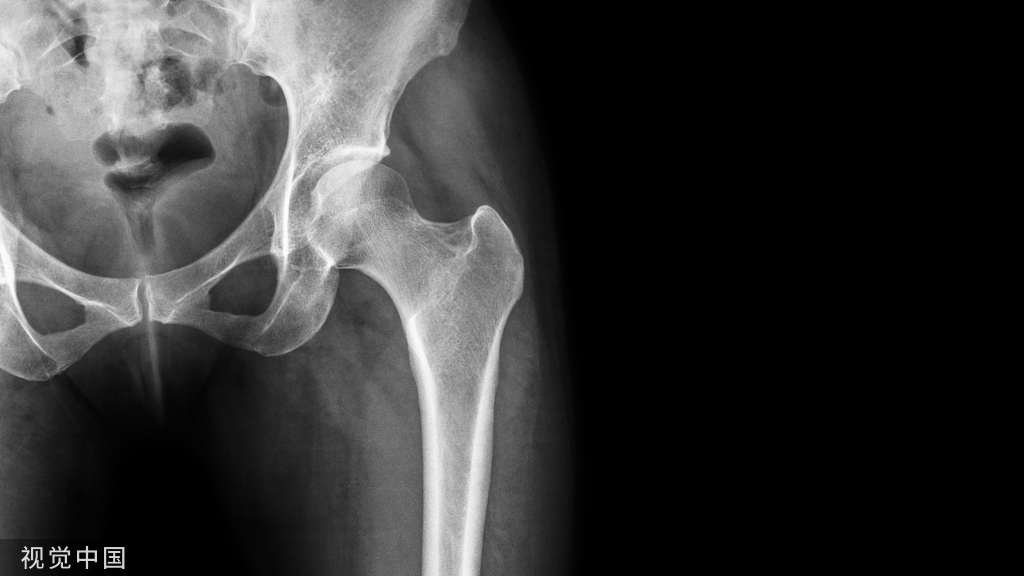

原发性骨质疏松症是一种以骨量降低、骨强度下降、骨折风险增加为特征的骨骼系统疾病。骨折可发生于任何骨骼中,其中髋部和脊柱骨折占所有骨质疏松性骨折的42%。骨折患者未来骨折的发生风险更高。